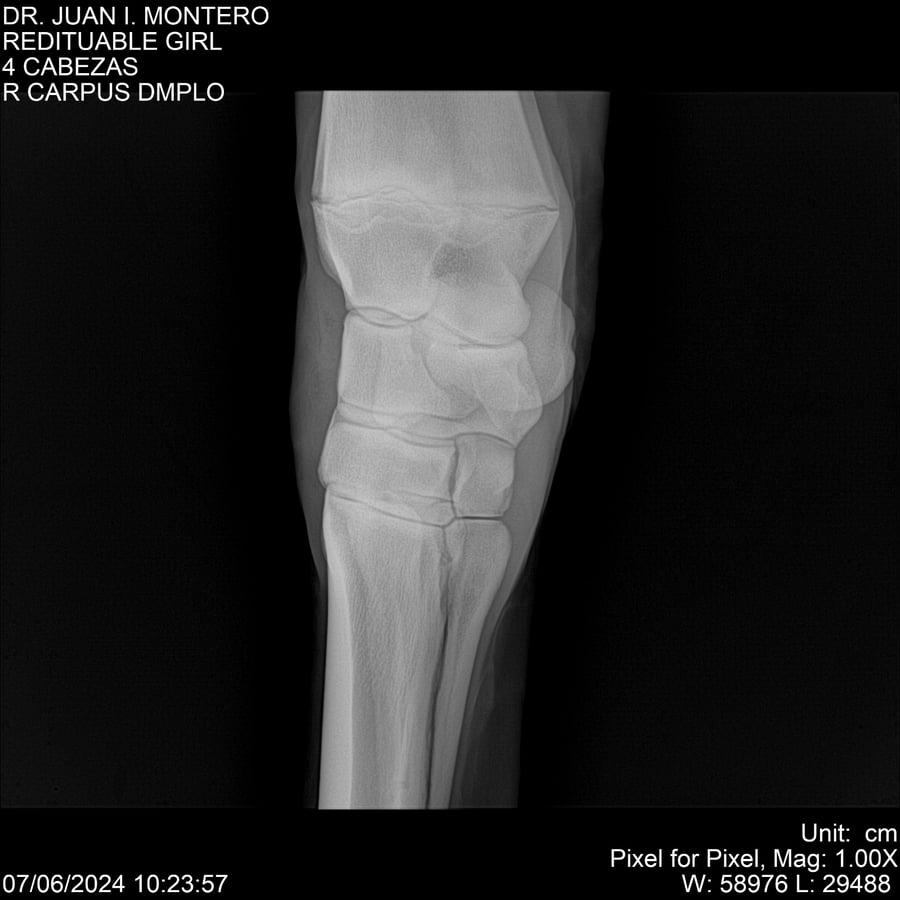

LOTE 19, REDITUABLE GIRL Lote Anterior Volver al remate Lote Siguiente Ficha Contacto Montevideo - Ficha del Lote Identificador: #281096 Categoría: Yeguarizos Montevideo - 79 Visualizaciones ClicData Contacto Empresa: Abelenda N. R., Walter Hugo Nombre*: Teléfono* : E-mail* : Mensaje Enviar Registrese gratis Este contenido Exclusivo está disponible sólo para usuarios registrados Ingresar